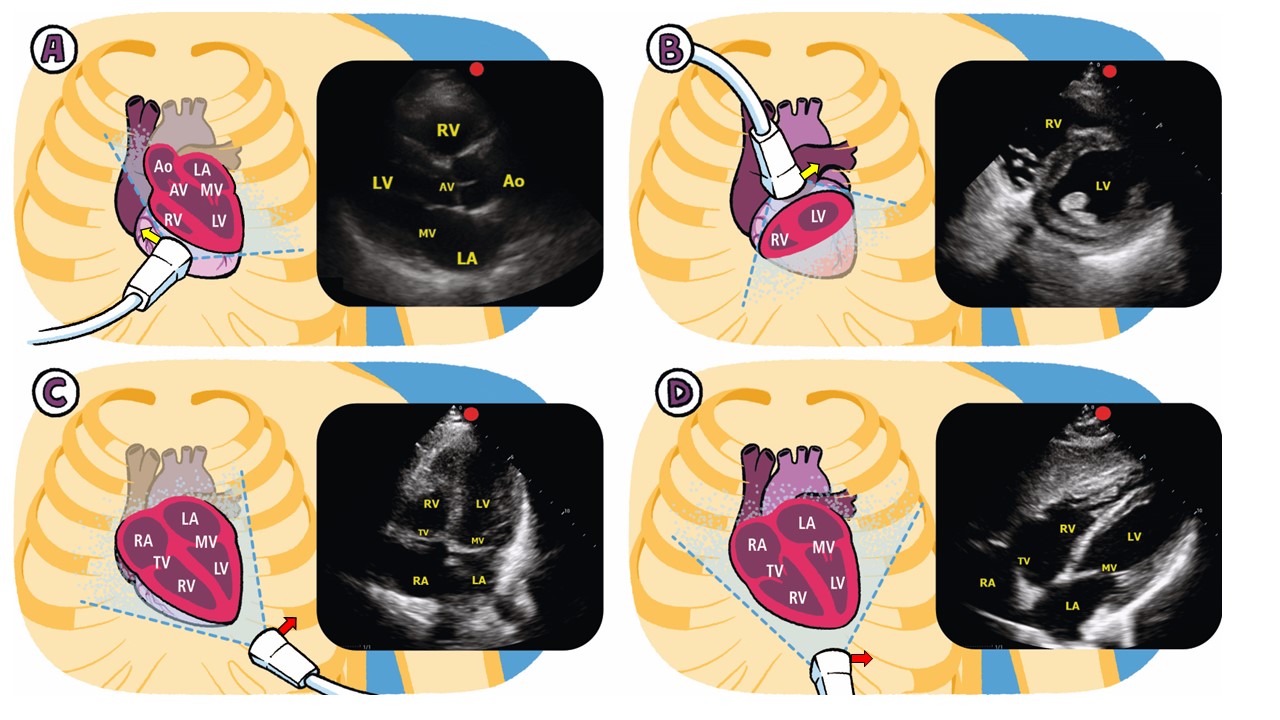

7.3 Vascular Pressures and the Pulmonary Artery Catheter